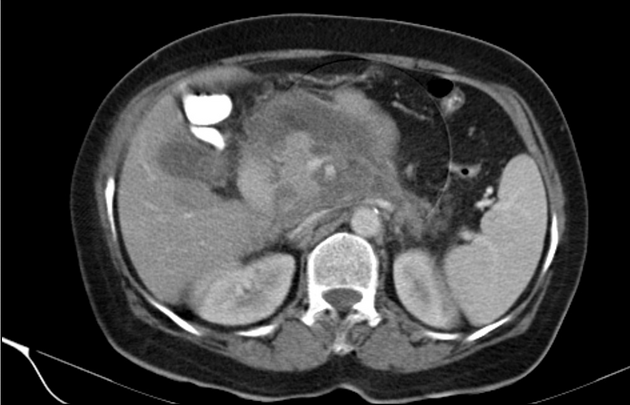

Είναι σημαντικό να πάτε στα επείγοντα αμέσως μόλις εμφανιστούν τα πρώτα συμπτώματα παγκρεατίτιδας. Ο γιατρός μπορεί στη συνέχεια να πραγματοποιήσει εξετάσεις για να ανιχνεύσει εάν τα επίπεδα των πεπτικών ενζύμων, των σακχάρων, του ασβεστίου και των λιπιδίων στο αίμα είναι πολύ υψηλά. Μια αξονική τομογραφία, η οποία είναι μια ακτινολογική εξέταση, μπορεί επίσης να συστηθεί για να απεικονίσει το οίδημα του παγκρέατος και/ή τη συσσώρευση υγρού. Τέλος, μια μαγνητική τομογραφία μπορεί να εντοπίσει την παρουσία χολόλιθων.